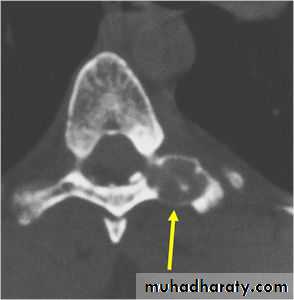

Its commoner in the spine and flat bones& usually presents as pain or muscle spasm.X-ray shows well-defined lytic lesion surrounded by thin zone of sclerosis, it may contain flecks of calcification.